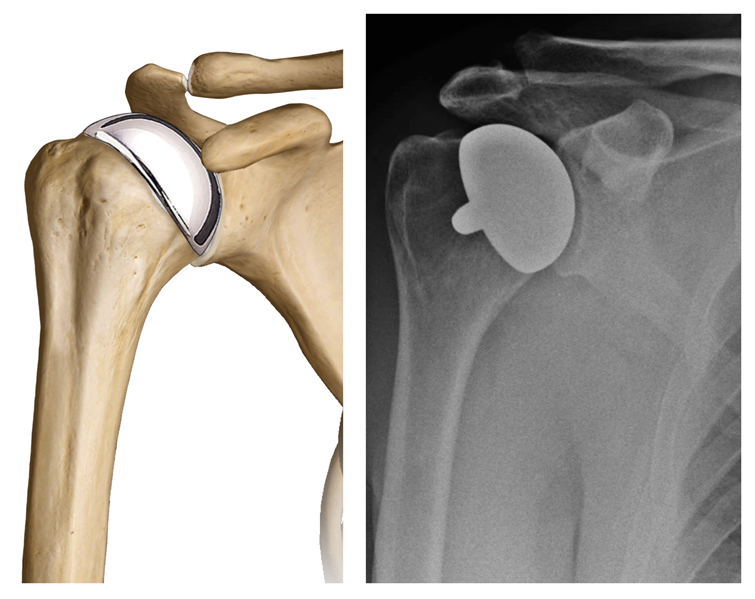

- Protesi totale di spalla (fig. 7): la tipica sostituzione totale della spalla comporta la sostituzione delle superfici articolari con elementi protesici in metallo e polietilene. I componenti sono disponibili in diverse dimensioni e possono essere cementati o non. Qualora l'osso fosse di buona qualità, il chirurgo può scegliere di utilizzare una componente omerale non cementata (press-fit); se invece l'osso si presentasse usurato, la componente omerale può essere impiantata con cemento. Nella maggior parte dei casi, viene impiantata anche una componente glenoidea in plastica.

- Protesi di spalla di rivestimento o “emicefalica” (fig. 8): comporta la sostituzione della superficie articolare della testa omerale con una protesi a cappuccio senza stelo. Può essere un'opzione valida se (a) la superficie articolare glenoidea è intatta; (b) il collo o la testa omerale non presentano fratture; (c) in pazienti giovani o molto attivi, evitando così i rischi di usura e allentamento delle componenti che potrebbero verificarsi con le sostituzioni convenzionali totali di spalla. Inoltre data la sua natura più conservativa, la protesi emicefalica può essere più facile da convertire in protesi totale di spalla quando necessario.